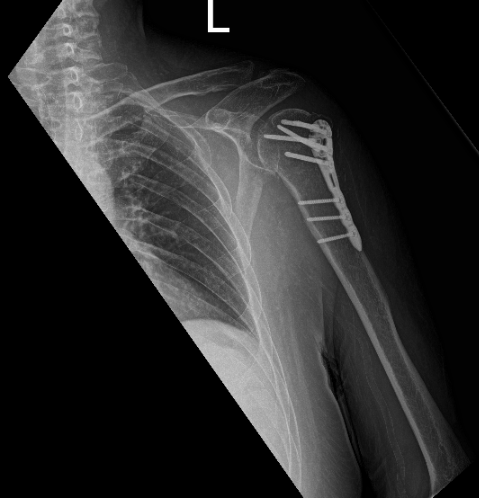

The patient is in status post-surgical repair of a comminuted fracture of the humeral head and neck. Fracture fragments are in good position and alignment. The surgical hardware is intact.

Patient last visit is 8 weeks after the operation, clearly seen on his X-ray that he is doing well with his surgery.